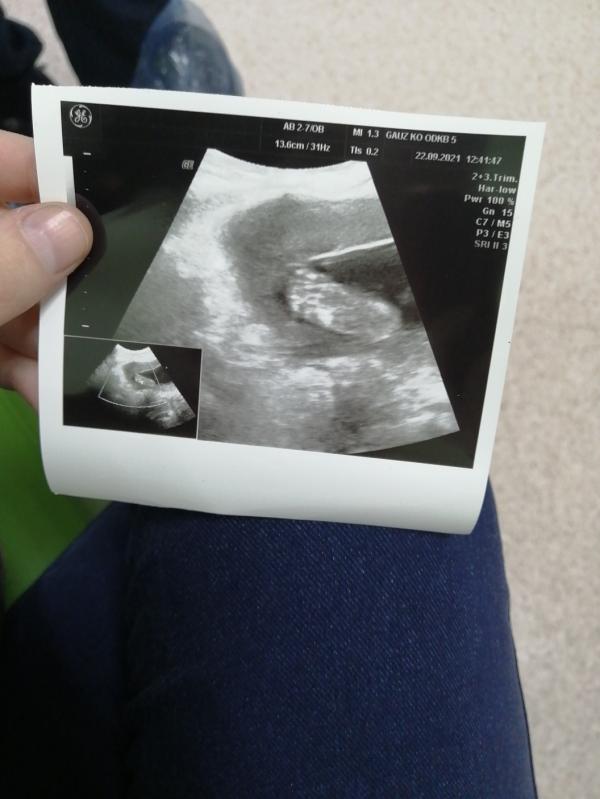

Вот узи на 20 недели, малыш дал сфотографировать только пяточку🥰